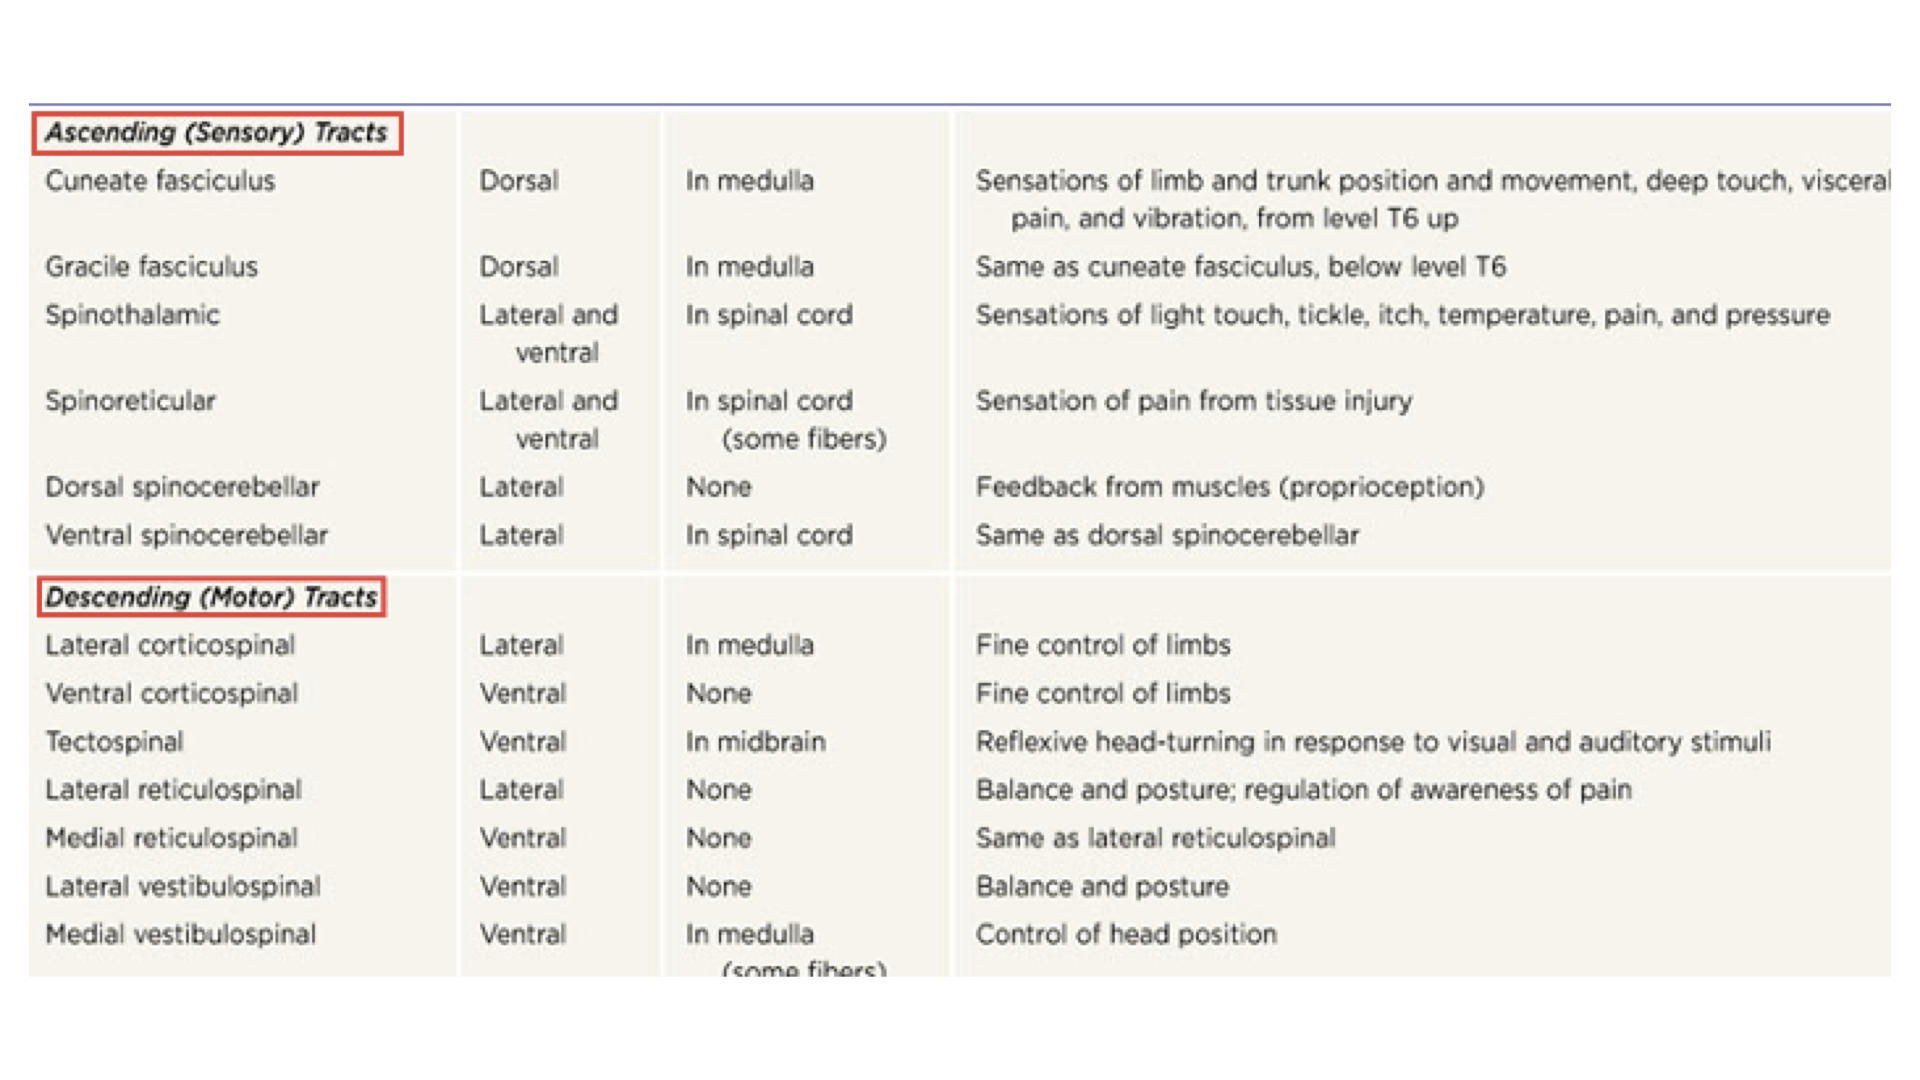

c. Ascending and descending tracts are located in the fasciculi

1. share common origins, destinations, and functions

d. A column is a group of tracts

e. Pathways

1. Ascending pathways have three neurons from sensor to cerebral cortex. Note that all go through the thalamus which serves as a filter.

Ascending Pathways

Ascending Pathways

2. Descending pathways have only two neurons between cerebral cortex and effector organ.

f. Decussation simply means the cross over between right and left. Remember that sensory data from right side of body and motor responses to the right side of the body involve the left cerebral hemisphere. Sensory and motor data from and to the left side of the body involve the right cerebral hemisphere.